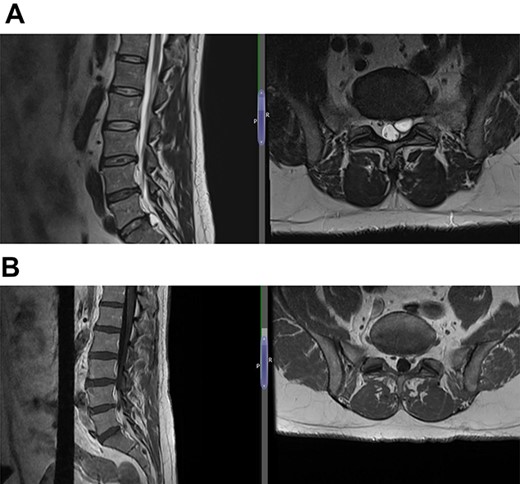

(A) Case 2—initial MRI shows a slightly unusual abnormality associated with the L5-S1 compressing the left transiting S1 nerve root and is almost certainly a fragment of extruded/sequestered disc, and (B) case 2—updated MRI shows a significant decrease in the previously seen cystic lesion at L5-S1 level now measuring 4 mm (AP diameter, previously 11 mm).